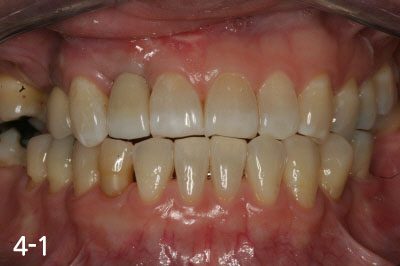

All implant crowns were fabricated and delivered. All teeth functions were restored.